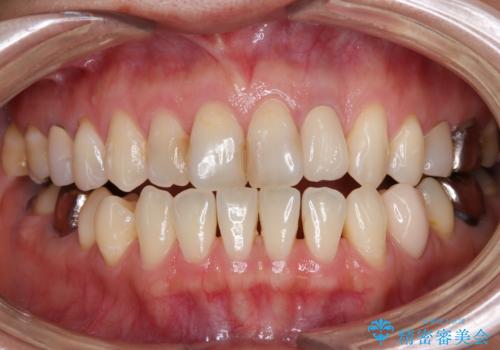

根元がうずく前歯 根管治療とオールセラミック治療

根管治療を行い、その後オールセラミッククラウンにて補綴治療を行うこととしました。

根管治療後速やかに痛みが消退し、6ヶ月後のレントゲン写真では、根尖部の病変がほぼなくなっていることが分かりました。